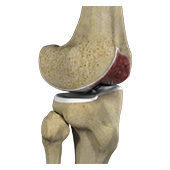

Patellofemoral Arthritis

Patellofemoral arthritis is an inflammatory condition characterized by loss of the smooth cartilage between the kneecap (patella) and the underlying femoral (thigh) bone in the knee joint. When the articular cartilage wears out, the underlying bones rub against each other, causing pain, swelling, stiffness, and restricted movement.